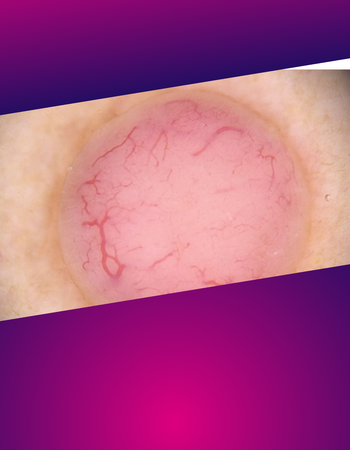

Diagnose-Quiz

Sieht man in der Ferne einen Vogel über die Kieler Bucht fliegen - was ist es wohl? Eine Möwe oder ein Kolibri? Oft liegt die Antwort scheinbar auf der Hand und das fast unmögliche wird gar nicht erst bedacht. So entpuppt sich manch harmloser Pickel erst auf den zweiten oder gar dritten Blick als echter Spezialfall. Andere Symptome sieht man einmal in zehn Jahren und kann sie deshalb evtl. nicht geich zuordnen... Unser Diagnose-Quiz fordert Dich mit ungewöhnlichen oder kniffligen Fällen heraus, die das Hirn so richtig auf Trab bringen.

Die Diagnosequizze werden uns freundlicherweise zur Verfügung gestellt vom "Journal der Deutschen Dermatologischen Gesellschaft" © Deutsche Dermatologische Gesellschaft